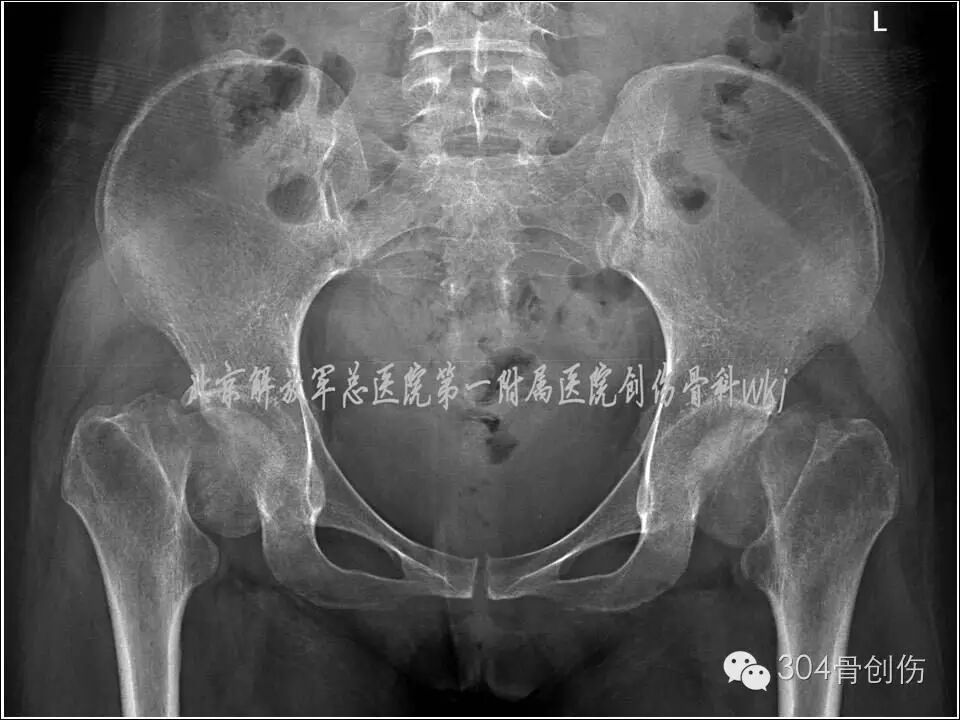

女,31岁,主因“双侧髋部疼痛活动受限6周”就诊。病史:患者孕36周时,扭伤跌倒,双髋部疼痛,活动受限,不能站立。X线显示:双侧股骨颈骨折,暂行保守治疗,待分娩后处理骨折。孕39周剖腹产一男婴,产后3周入304创伤骨科治疗。入院查体:体重50kg,身高156cm,双下肢外旋畸形,双大腿近端前外侧压痛,双下肢纵向叩击痛阳性,诊断:双侧股骨颈陈旧性骨折(Garden Ⅳ型-图)。

图-患者伤后X线片

(盆腔内为胎儿头颅)